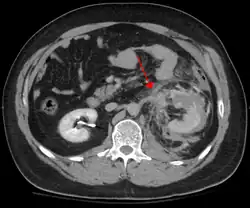

CT abdominal montrant une lésion de l'artère rénale gauche

Le traumatisme abdominal contondant (TAC) représente 75 % de tous les traumatismes contondants et constitue l'exemple le plus courant de cette blessure[4]. 75 % des TAC surviennent lors des accidents de la route[5], dans lesquels une décélération rapide peut propulser le conducteur contre le volant, le tableau de bord ou la ceinture de sécurité[6], provoquant des contusions dans les cas moins graves, ou la rupture d'organes internes en raison d'une brève augmentation de la pression intraluminale dans les cas les plus graves, en fonction de la force appliquée. Au début, il peut y avoir peu d'indications que des lésions abdominales internes graves se sont produites, ce qui rend l'évaluation plus difficile et exige un haut degré de suspicion clinique[7].

La décélération, en revanche, provoque un étirement et un cisaillement aux points d'ancrage du contenu mobile de l'abdomen, comme l'intestin. Cela peut provoquer une déchirure du mésentère de l'intestin et des lésions des vaisseaux sanguins qui parcourent le mésentère. Des exemples classiques de ces mécanismes sont une déchirure hépatique le long du ligament rond et des lésions des artères rénales.